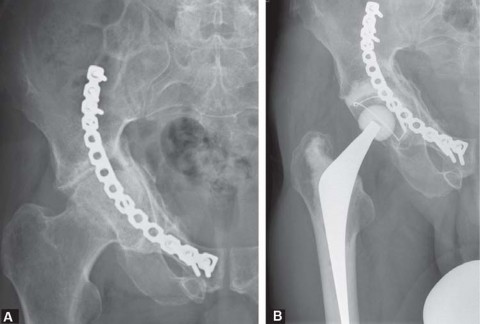

<img alt="وصف طبي دقيق للمريض" class="img-fluid rounded shadow-sm d-block mx-auto my-4" loading="lazy" src="/media/upload/a7dbb80a-49c5-4b41-b295-430553bad3e7.jpg" style="max-height: 600px